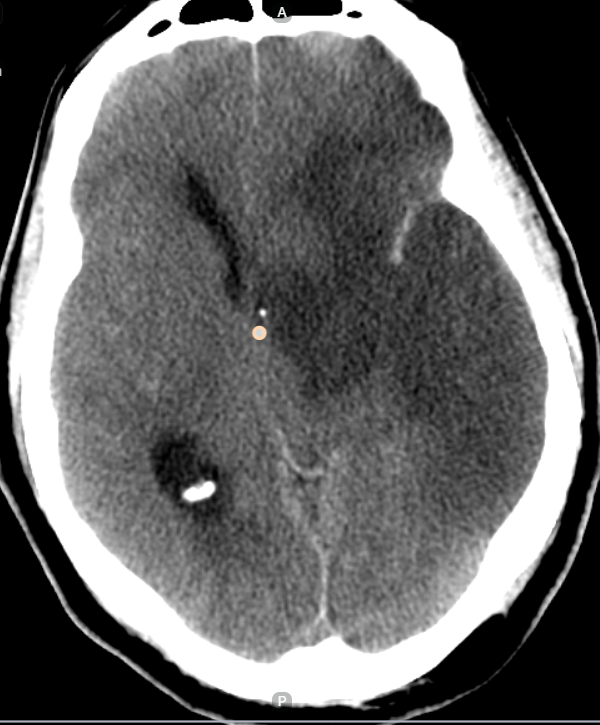

We provided a range of annotation services, such as landmark annotations, disease-wise annotations, and pixel-wise segmentation. Depending on the needs of the AI models being created, each category had a different purpose. Our careful annotation approach made sure that the training data was accurate and complete, which improved model performance. We had experience annotating a wide range of disease pathologies, including coronary artery calcification and obstructive hydrocephalus. We have an experienced team with numerous years of experience to carry out precise annotations and contribute to the development of excellent AI models.

Medical image annotation is the process of labeling medical images, such as X-rays, MRIs, CT scans, and ultrasound images, to help AI models recognize patterns and abnormalities. This process involves trained radiologists, pathologists, and data annotators who precisely mark anatomical structures, tumors, and other critical elements within medical images.

- Early Disease Detection: AI models trained on accurately annotated medical images can detect diseases like cancer, pneumonia, and neurological disorders at an early stage.

- Improved Diagnostics: Machine learning image annotation enables AI models to analyze medical scans with high precision, reducing diagnostic errors.

1. Segmentation Annotation

- Identifies and labels different regions within a medical image, such as tumors, organs, and tissues.

- Used in oncology, cardiology, and neurology for precise diagnosis.